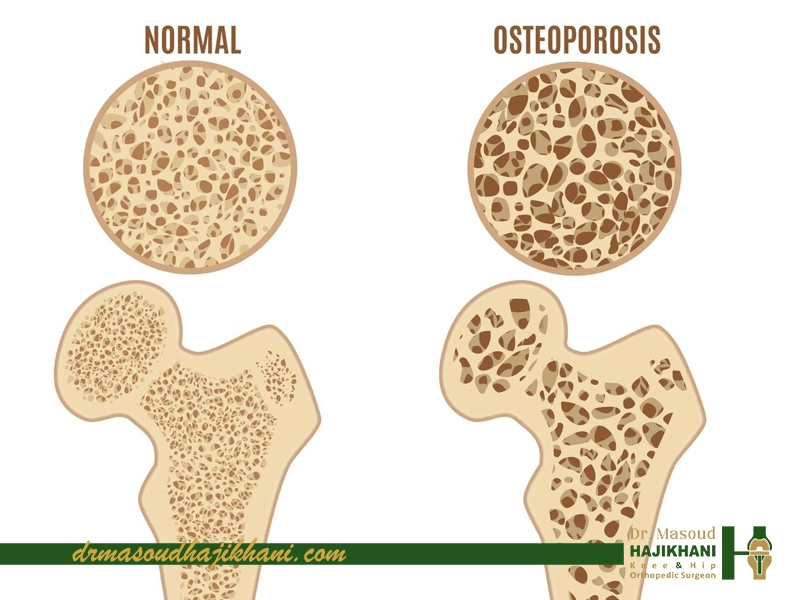

پوکی استخوان بهطور مستقیم باعث لاغری نمیشود. این بیماری فقط بر تراکم استخوان اثر میگذارد و ماهیت آن کاهش وزن یا کم شدن چربی بدن نیست. اما برخی شرایط همراه پوکی استخوان میتوانند باعث کاهش وزن شوند یا شکل بدن را طوری تغییر دهند که فرد «احساس لاغری» کند، حتی اگر وزن او روی ترازو کم نشده باشد.

برخلاف اینکه پوکی استخوان سبب لاغری شود، لاغری شدید خودش یکی از عوامل خطر اصلی پوکی استخوان است. BMI پایین، مصرف کم مواد مغذی، کمبود چربی بدن (بهخصوص در خانمها که باعث افت هورمون استروژن میشود) و رژیمهای سخت، همگی میتوانند تراکم استخوان را کاهش دهند.